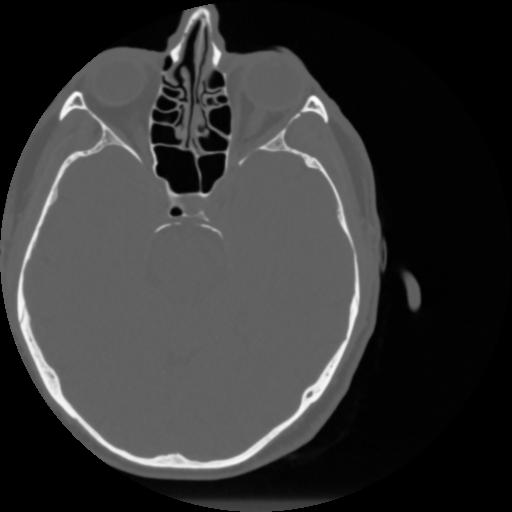

4 CEREBRO,,Vol,0.5,CEREBRO,,